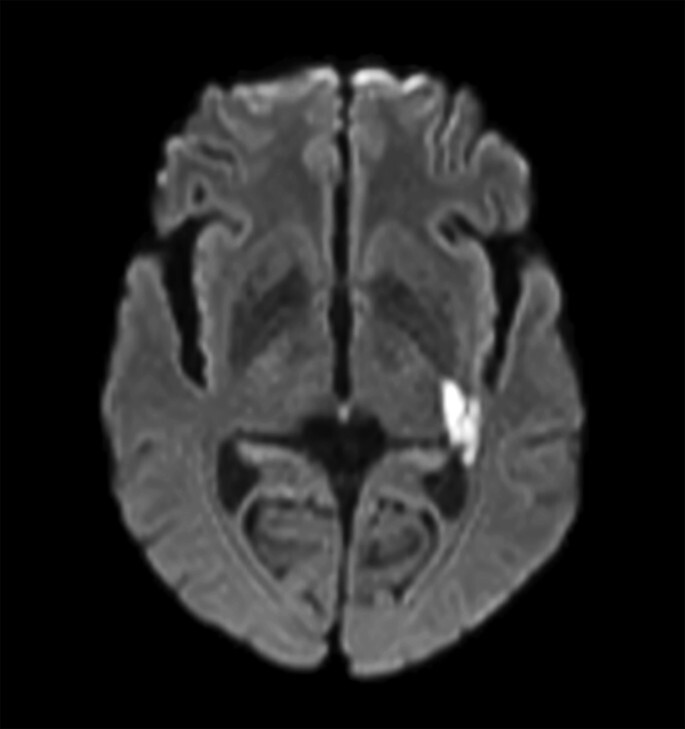

脳梗塞 臨床画像

【イラスト解説】脳梗塞のタイムリミット